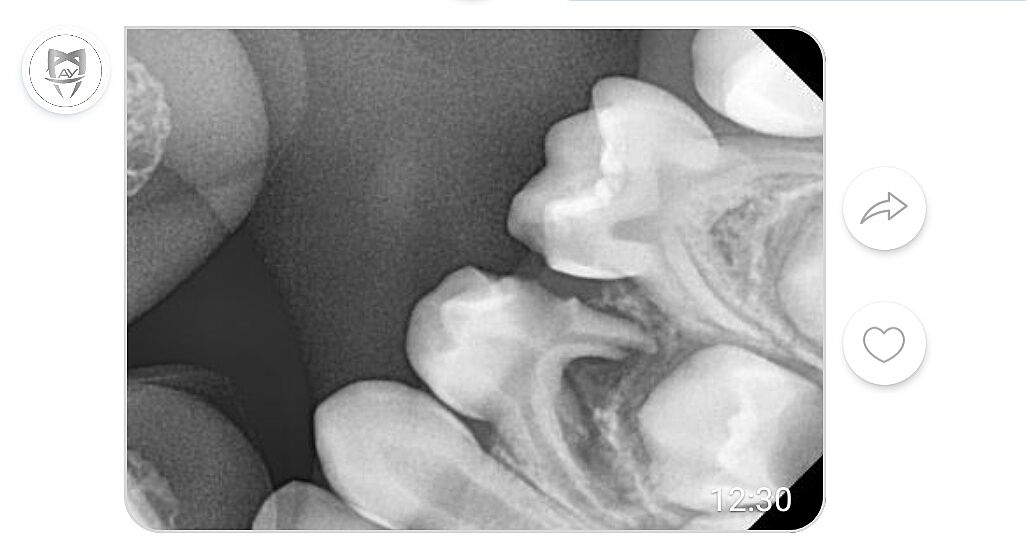

Так видно? прийшлося з вайбера скріншот зробити, бо електроенергію вимкнули, інтернет поганий. Дуже Вам дякую

attached-photo

Видно. Інший корінь довгий і він не розсмокчеться ні через місяць ні через рік. Полоскання нічого не дасть, зуб іде на видалення. Запальний процес може зруйнувати захисну оболонку цього зуба. Знеболити його важкувато, бо інший корінь ще довгий. Треба робити провідникову анестезію при якій замерзає півщоки і пів язика. Плюс ще глибокий карієс в сусідньому п ятому зубі. Враховуючи, що дитина налякана і всього 5 рокіі, то варіантів 2

1. Пробувати під маскою ЗАКС гарно знеболити і пооікувати 5 і видалити 4 в один візит. Потім обов язково утримувач місця.

2. Зробити знімки всіх зубів, виявити всі проблеми і йти в наркоз, теж потім обов язково утримувач місця.